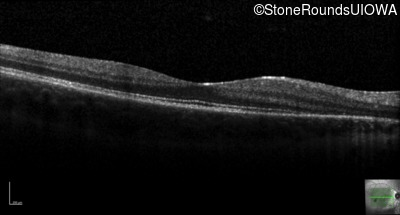

Age at visit: 14 years

Age at visit: 15 years

Age at visit: 16 years

Age at visit: 18 years

Age at visit: 18 years (Visit 2)

Age at visit: 19 years

Age at visit: 20 years

Age at visit: 22 years